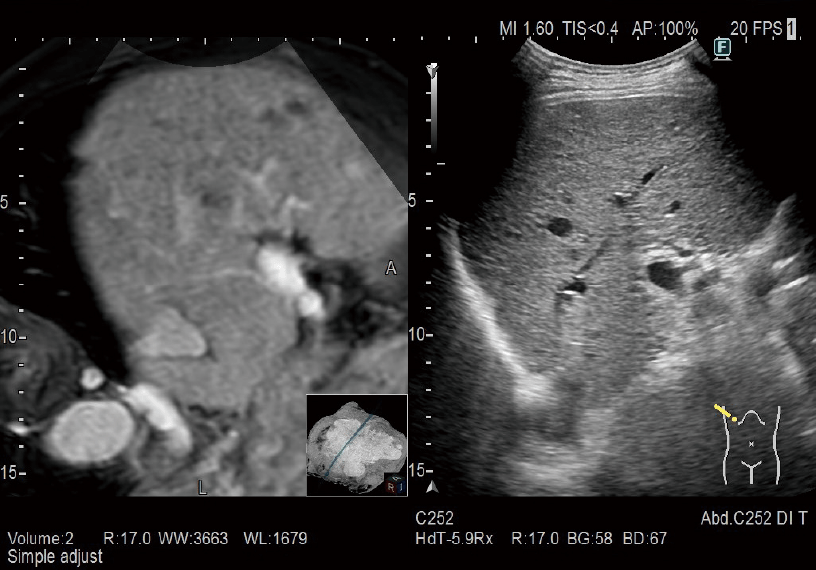

MPR images constructed from CT/MRI/PET-CT/US volume data can be synchronized to real-time ultrasound imaging. It is applied in a wide variety of clinical fields: such as for Abdomen, Breast, navigation in prostate puncture, and so on.